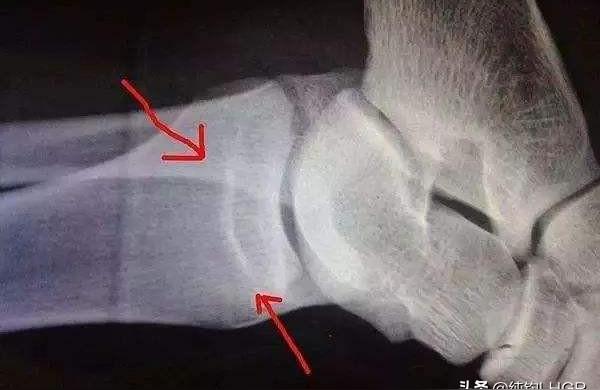

骨骺线是骨骺板的截面影像,在X光片上表现为一条较宽的透光带,它随着年龄的增长而逐渐变窄。长骨干骺端与骨骺之间有一盘状软骨结构,称为骺板,骺板逐渐骨化,而骨骺与干骺端的软骨完全骨化后,就形成一条紧密的缝,此时骨骺线完全闭合,骨骼停止生长。

从图片上来说,箭头所指,即为骨骺线。图片上就是已经闭合的情况。

骨化过程从X线表现分为三个阶段,即干骺愈合前、干骺部分愈合和干骺完全愈合,愈合前干骺端先期钙化带呈波浪状或锯齿状,常伴有硬化;部分愈合是指骨骺和干骺端大部分愈合,仅少部分愈合前,干骺完全愈合,即骨化完成。女孩15~16岁完全骨化者占93%左右,男孩较女孩发育早两年。